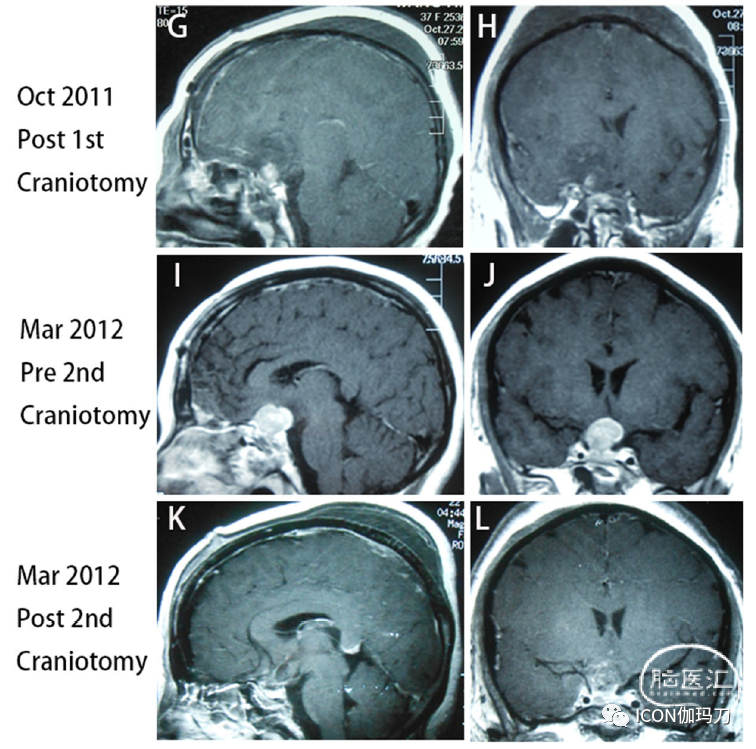

34岁女性,2009年12月因头痛、闭经和溢乳入院。原始血清泌乳素水平为700.0 ng/mL(补充图1),MRI显示2.x2.0 cm垂体大腺瘤,侵袭右侧海绵窦,完全包裹右侧颈内动脉(ICA) (Knosp分级4级)(图1A和B)。然后行经蝶窦手术(TSS),行全切除术(图1C和D)。根据病理报告诊断为泌乳素瘤,Ki-67标记指数(LI)为3%。但病理切片无法从其他医院获得。术后头痛、闭经、溢乳等症状明显改善,泌乳素水平降至正常范围(补充图1)。术后垂体激素水平基本正常。在术后随访中,患者出现急性右侧视力下降,MRI报告肿瘤迅速扩大并压迫视交叉(图1E和F),血清逆乳素水平再次上升至356.0 ng/mL(补充图1)。2011年10月,患者首次行额部开颅手术。肿瘤亚全切除(图1G和H),术后视力减退症状明显改善,血清泌乳素水平降至356.0 ng/mL(补充图1)。术后患者给予醋酸去氨加压素0.1 mg/d治疗尿崩症。垂体前叶功能基本正常。不幸的是,她又出现视力丧失,2012年3月和磁共振表明快速增长的肿瘤压迫视交叉和侵袭第三脑室(图1 I和J)和血清泌乳素水平增加到200.0 ng / mL(样本不稀释)又(补充图。1)。她接受了第二次经额开颅术后,视力减退症状明显改善,血清泌乳素水平再次降至37.0 ng/mL(补充图1)。然而,实验室结果显示血清皮质醇水平下降0.08 μg/dl(参考文献:5.7 -22.6 μg/dl), GH水平0.01 μg/L(参考值:1- 4,6 μg/L),总T4水平30.21 nmol/L(参考值:75-150 nmol/L),游离T4水平4.07 pmol/L(参考值:7.5-15 pmol/L)。患者给予醋酸强的松30 mg /天,左旋甲状腺素钠100 μg /天,垂体前叶激素水平基本恢复正常。从那以后,她接受了永久性的激素替代疗法。

图1.术前矢状位(A)和冠状位(B)磁共振成像(MRI)显示垂体大腺瘤2.5厘米* 2.0厘米,侵袭海绵窦,完全包裹右侧颈内动脉(ICA)(Knosp4级)。(C)和(D)三个月后第一次蝶手术(TSS),MRI显示肿瘤被完全切除。(E)和(F)在第一次经额开颅前,2011年10月MRI显示一个迅速扩大的肿瘤,并压迫视交叉。(G)和(H)第一次经额开颅后,MRI显示肿瘤近全切除。(I)和(J)第二次开颅前,2012年3月MRI显示肿瘤快速生长,视神经视交叉受压,侵袭第三脑室。(K)、(L)第二次经额开颅后,肿瘤次全切除。